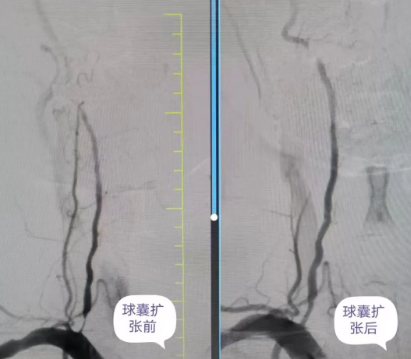

神經(jīng)介入團(tuán)隊(duì)術(shù)前與患者及其家屬詳細(xì)溝通,并告知手術(shù)為微創(chuàng)手術(shù),相較于傳統(tǒng)手術(shù)具有恢復(fù)時(shí)間短、并發(fā)癥少等優(yōu)勢(shì)?;颊吆图覍僭诔浞至私馇闆r后,表示對(duì)國(guó)文醫(yī)院神經(jīng)介入科非常信任,同意手術(shù)。神經(jīng)介入科團(tuán)隊(duì)在完善術(shù)前準(zhǔn)備后,對(duì)患者進(jìn)行了右側(cè)椎動(dòng)脈起始段的球囊擴(kuò)張手術(shù)。

術(shù)中,丁金明主任、朱洪波副主任帶領(lǐng)團(tuán)隊(duì),通過(guò)導(dǎo)管精準(zhǔn)地將球囊送至狹窄的椎動(dòng)脈段,在確認(rèn)球囊位置準(zhǔn)確無(wú)誤后,仔細(xì)地進(jìn)行擴(kuò)張,直至狹窄的血管恢復(fù)到接近正常直徑。整個(gè)手術(shù)過(guò)程在專業(yè)團(tuán)隊(duì)的精心操作下,僅30分鐘便順利完成。